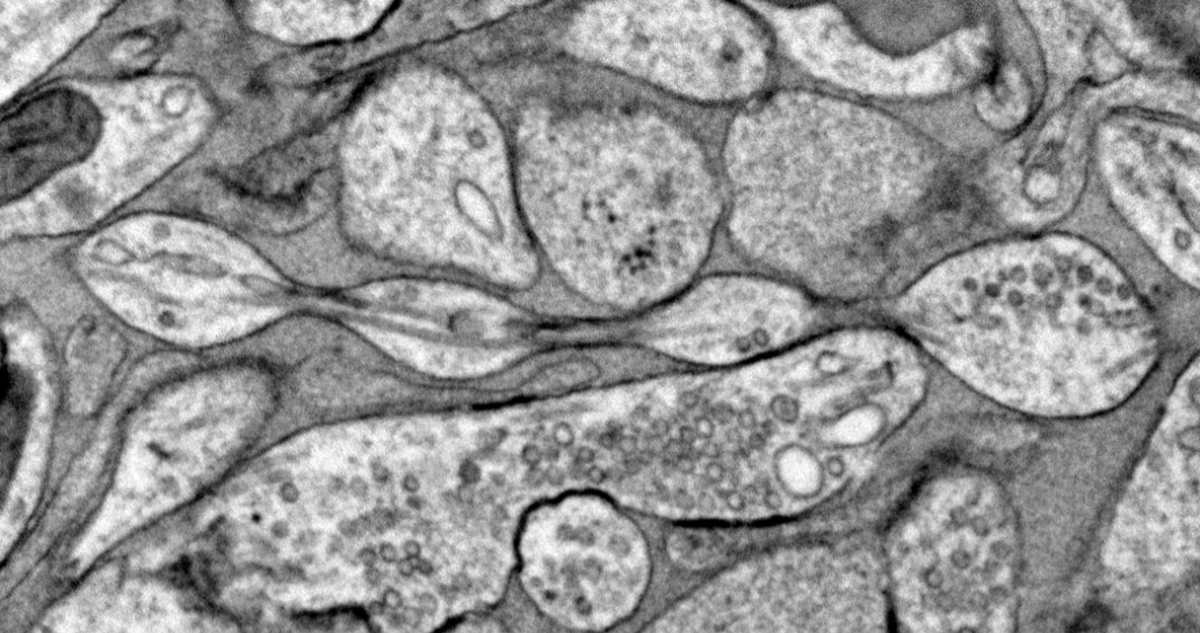

Imagen microscópica de neuronas de ratón preservadas con la técnica de congelación a alta presión | Johns Hopkins Medicine

Su estudio, basado en neuronas de ratones, encontró que los axones, que son los “brazos” que se extienden entre células cerebrales e intercambian información, no son como tubos cilíndricos, sino que podrían tener la forma de un collar de perlas.

Sin embargo, el método de Griswold asegura ser diferente, ya que preparó las células con una técnica de “congelación a alta presión”, que puede preservar la estructura fina de las neuronas.

Así, con un microscopio electrónico, vio que los bultos de 200 nanómetros de diámetro, distribuidos uniformemente a lo largo de los axones de los ratones, no eran como las bolitas producidas por atascos. De hecho, no tenían nada dentro.